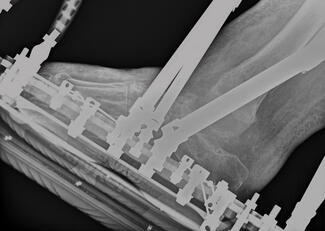

Harry John Visser, DPM, FACFAS; Nicole Marie Smith, DPM

Early identification of, and treatment for, talar avascular necrosis is key to successful outcomes. However, when patients with diagnostic delay present to the office, treatment pathways are not always linear. Here the authors present a...